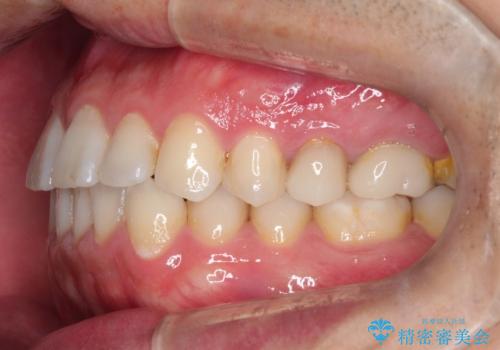

【インビザライン】前歯の隙間を閉じたい

- 前歯の隙間を主訴に来院されました。

マウスピース矯正にて、隙間を綺麗に閉じることができ満足していただきました。

前歯の隙間を閉じる際は、前歯部の突き上げが懸念されるため、適切な治療計画が必要となります。